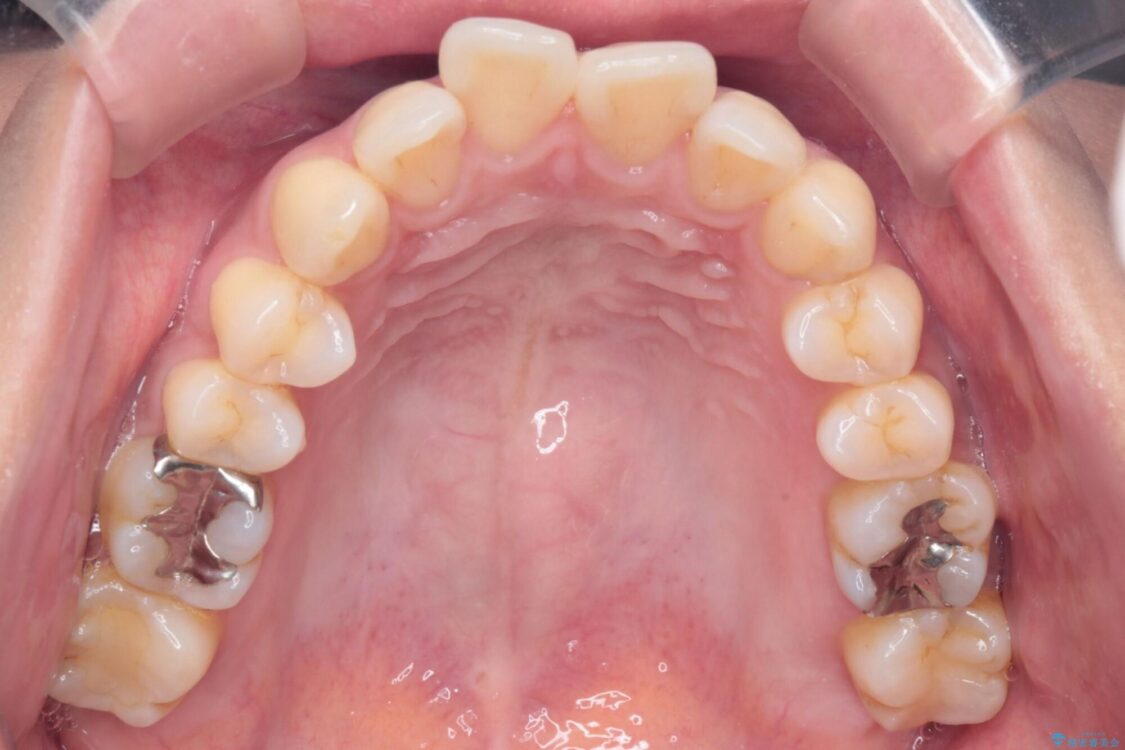

上の前歯の突出感を気にして来院された患者様です。

目立たない装置を希望とのことで、上顎左右第一小臼歯を抜歯し、インビザラインにて矯正治療を行うこととしました。

治療前

• 上顎前歯の突出を軽減 インビザラインによる抜歯矯正 治療前画像